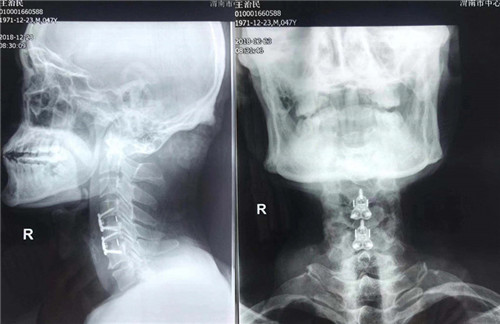

术前

术后